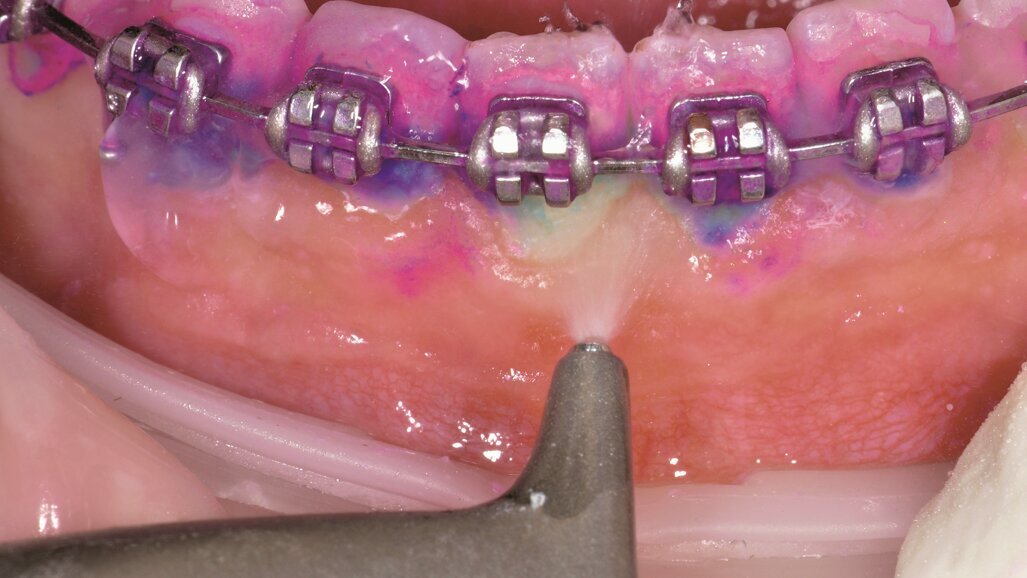

Kombinace všech výše uvedených problémů způsobila, že jsem chtěla najít lepší řešení. Zjistila jsem, že použití AIRFLOW v kombinaci s postupem Guided Biofilm Therapy přináší ohromující výsledky. Pokud byste se mě dříve zeptali na AIRFLOW pro odstranění biofilmu, asi bych si myslela, že jste se zbláznili nebo mě nenávidíte. Před AIRFLOW jsem nechtěla barvit plak u pacientů, kteří měli ortodontické aparáty – ukázalo by se, že existují oblasti, kde jsem ponechala biofilm, protože jsem se k němu nemohla dostat. Teď detekuji plak obarvením u každého pacienta jako součást protokolu Guided Biofilm Therapy.

Díky protokolu Guided Biofilm Therapy je možné dosáhnout odstranění biofilmu ve 100 % s 360° přístupností. Je bezpečné a účinné okolo gingiválního sulku, neničí povrch aparátu a také je mnohem pohodlnější pro pacienta a přináší lepší výsledky. Nejen já, ale i pacient vidíme kvalitnější výsledky, je také klinicky dokázáno, že použití detekčního roztoku zajistí pacientovi lepší výsledky. Botti a kol. (2010)3, Bastendorf a kol. (2016)4 a Viorica a kol. (2013)5 – všichni potvrzují vyšší účinnost profesionální profylaxe při použití prostředku na detekci plaku. Ve studii Viorica a kol. Zubní povlak – Klasifikace, Tvoření a Identifikace5 bylo zjištěno, že: „…diagnostika zubního povlaku za použití barevných roztoků je jednou z nejjednodušších a nejrychlejších cest k rozpoznání zubního povlaku, což usnadňuje jeho následné odstranění za soustavné kontroly během zákroku. Použití AIRFLOW zvyšuje úspěšnost odstranění povlaku na 100 %...”

Existují dva klíčové důvody, proč je aplikace Guided Biofilm Therapy důležitá pro ortodontické pacienty. První z nich je dlouhodobé zdraví skloviny a dásní. S použitím AIRFLOW technologie kombinované s AIRFLOW PLUS práškem vím, že zajišťuji nejšetrnější ošetření skloviny pacienta a jeho ortodontického aparátu. V Klinickém srovnání účinnosti a efektivity dvou profesionálních profylaktických postupů u ortodontických pacientů6 Ramaglia a kol. ukazují, že: „…u ortodontických pacientů je použití AIRFLOW mnohem bezpečnější, účinnější a efektivnější k odstranění pigmentací a biofilmu ve srovnání s gumovými kalíšky a pemzou…” Druhá skvělá věc je, že mám nyní čas vše stihnout v rámci běžné kontroly. Necítím se už tolik pod „tlakem”. Ve studii Účinky air-polishingu na zuby opatřené ortodontickými zámky a kroužky7 Barnes a kol. ukazují, že: „…pískování v okolí ortodontických zámků a kroužků není jen účinné, ale také šetří čas. Nebyly zaznamenány žádné škodlivé účinky na kompozitní materiály nebo cement v porovnání s gumovými kalíšky nebo pemzou…”